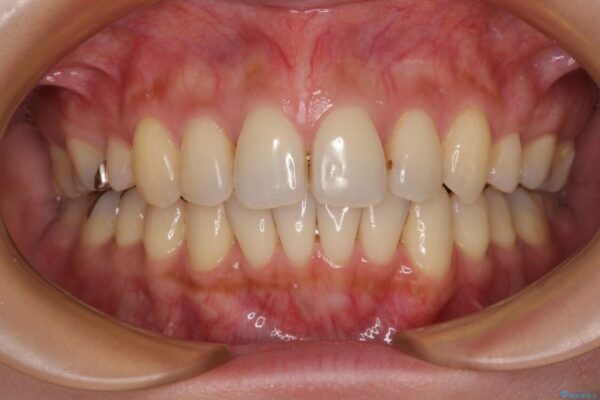

上の前歯の突出感を気にして来院された患者様です。

目立たない装置を希望とのことで、上顎左右第一小臼歯を抜歯し、インビザラインにて矯正治療を行うこととしました。

治療前

• 上顎前歯の突出を軽減 インビザラインによる抜歯矯正 治療前画像